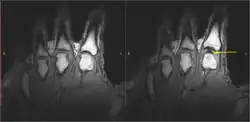

Einer Theorie und Untersuchung der Forscher J. B. Roston und R. Wheeler Haines aus dem Jahre 1947 nach werden im Gelenk die glatten Knorpelflächen durch einen dünnen Film aus sogenannter Gelenkschmiere (Synovialflüssigkeit) voneinander getrennt. Wenn man das Gelenk überdehnt, wird in der Gelenkkapsel ein Unterdruck erzeugt. Dabei werden schlagartig in der Flüssigkeit gelöste Gase frei (Kavitation). Zu diesem Zeitpunkt knackt es. Der Hohlraum, welcher durch den Unterdruck entsteht, bleibt jedoch noch einige Zeit. Nach einigen Minuten, wenn das Gas wieder gelöst ist, kann der Vorgang wiederholt werden.[1]

Diese Theorie wurde in einem 2015 veröffentlichten wissenschaftlichen Artikel unter anderem von Gregory N. Kawchuk bestätigt. Zugleich wurde eine Theorie aus dem Jahre 1971, welcher zufolge das Knacken durch das Zerplatzen der Blasen entsteht, widerlegt.[2][3]